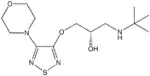

Propanolamines are a class of chemical compounds, many of which are pharmaceutical drugs. They are amino alcohols that are derivatives of 1-amino-2-propanol.[1]

Propanolamines include: